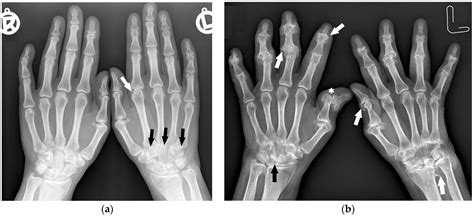

Sex X Ray technology involves the use of X-rays to produce images of the internal structures of the reproductive and sexual organs. This type of imaging is particularly useful for diagnosing conditions that affect the reproductive system, such as tumors, infections, and anatomical abnormalities. The technology works by passing X-rays through the body, which are then captured on a detector to create detailed images.

- Detecting Tumors and Cancers: X-rays can reveal the presence of tumors or cancers in the reproductive organs, allowing for early detection and treatment.

- Evaluating Anatomical Abnormalities: Conditions such as uterine fibroids, ovarian cysts, and other anatomical issues can be diagnosed using Sex X Ray technology.

- Assessing Infections: Infections in the reproductive system, such as pelvic inflammatory disease (PID), can be identified through detailed imaging.

Interpreting Sex X Ray results requires the expertise of a radiologist. The images are carefully analyzed to identify any abnormalities or conditions. Here are some common findings:

| Tumors or Masses | Cancer, Benign Tumors |

| Anatomical Abnormalities | Uterine Fibroids, Ovarian Cysts |

| Infections | Pelvic Inflammatory Disease (PID), Sexually Transmitted Infections (STIs) |